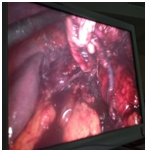

Under General Anaesthesia, the patient was placed in right semi lateral position. A primary 10mm port placed supraumbilically for a telescope. A 10mm port placed in the left midclavicular line. Two 5mm ports placed in the midclavicular line and in the sub xiphisternal region for working elements. A monitor, Co2 pneumoperitoneum (12mmHg), a laparoscope (HD KARL STORTZ,GERMANY), an ultrasonic dissector, Thunder beat (OLYMOPUS,GERMANY) and routine laparoscopic instruments were used. The giant retroperitoneal mass seen pushing left kidney downwards and bowels anteriorly. Retroperitoneal approach was palnned. The descending colon is dissected and brought medially. The left suprarenal area is started dissecting out very carefully. All around the mass dissection done and freed from surrounding structures .Artery and vein to the mass identified separately, clipped and ligated (Figure 2). Retroperitoneal mass specimen was brought out into from the left side of abdomen, infraumbilically. Haemostasis secured. Drain placed and fixed. Port closure done. Postoperative recovery was uneventful and on fifth post op day, he was discharged from the hospital with complete recovery. The pathological analysis demonstrated Spindle cell neoplasm composed of alternatively hypo cellular areas with marked nuclear palisading, well formed verocay body and hyper cellular areas with edema (Figure 3A-C). Immuno Histo Chemical staining clarified that the neoplastic cells were strongly positive for s100 protein (Figure 3D), while CD117(C-Kit), SMA (Smooth Muscle Actin), Desmin, PDGFR (Platelet Derived Growth Factor Receptor) were negative.

Figure 2 Artery and vein to the mass identified separately, clipped and ligated.